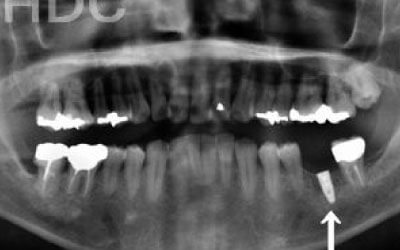

2 歯が傾いてくる、落ちてくる

歯は互いに支え合ってバランスを保っています。つまり、歯が抜けるとその支えがなくなり、抜けた部分の隣の歯が倒れたり、上の歯が下に沈んだりすることがあります。